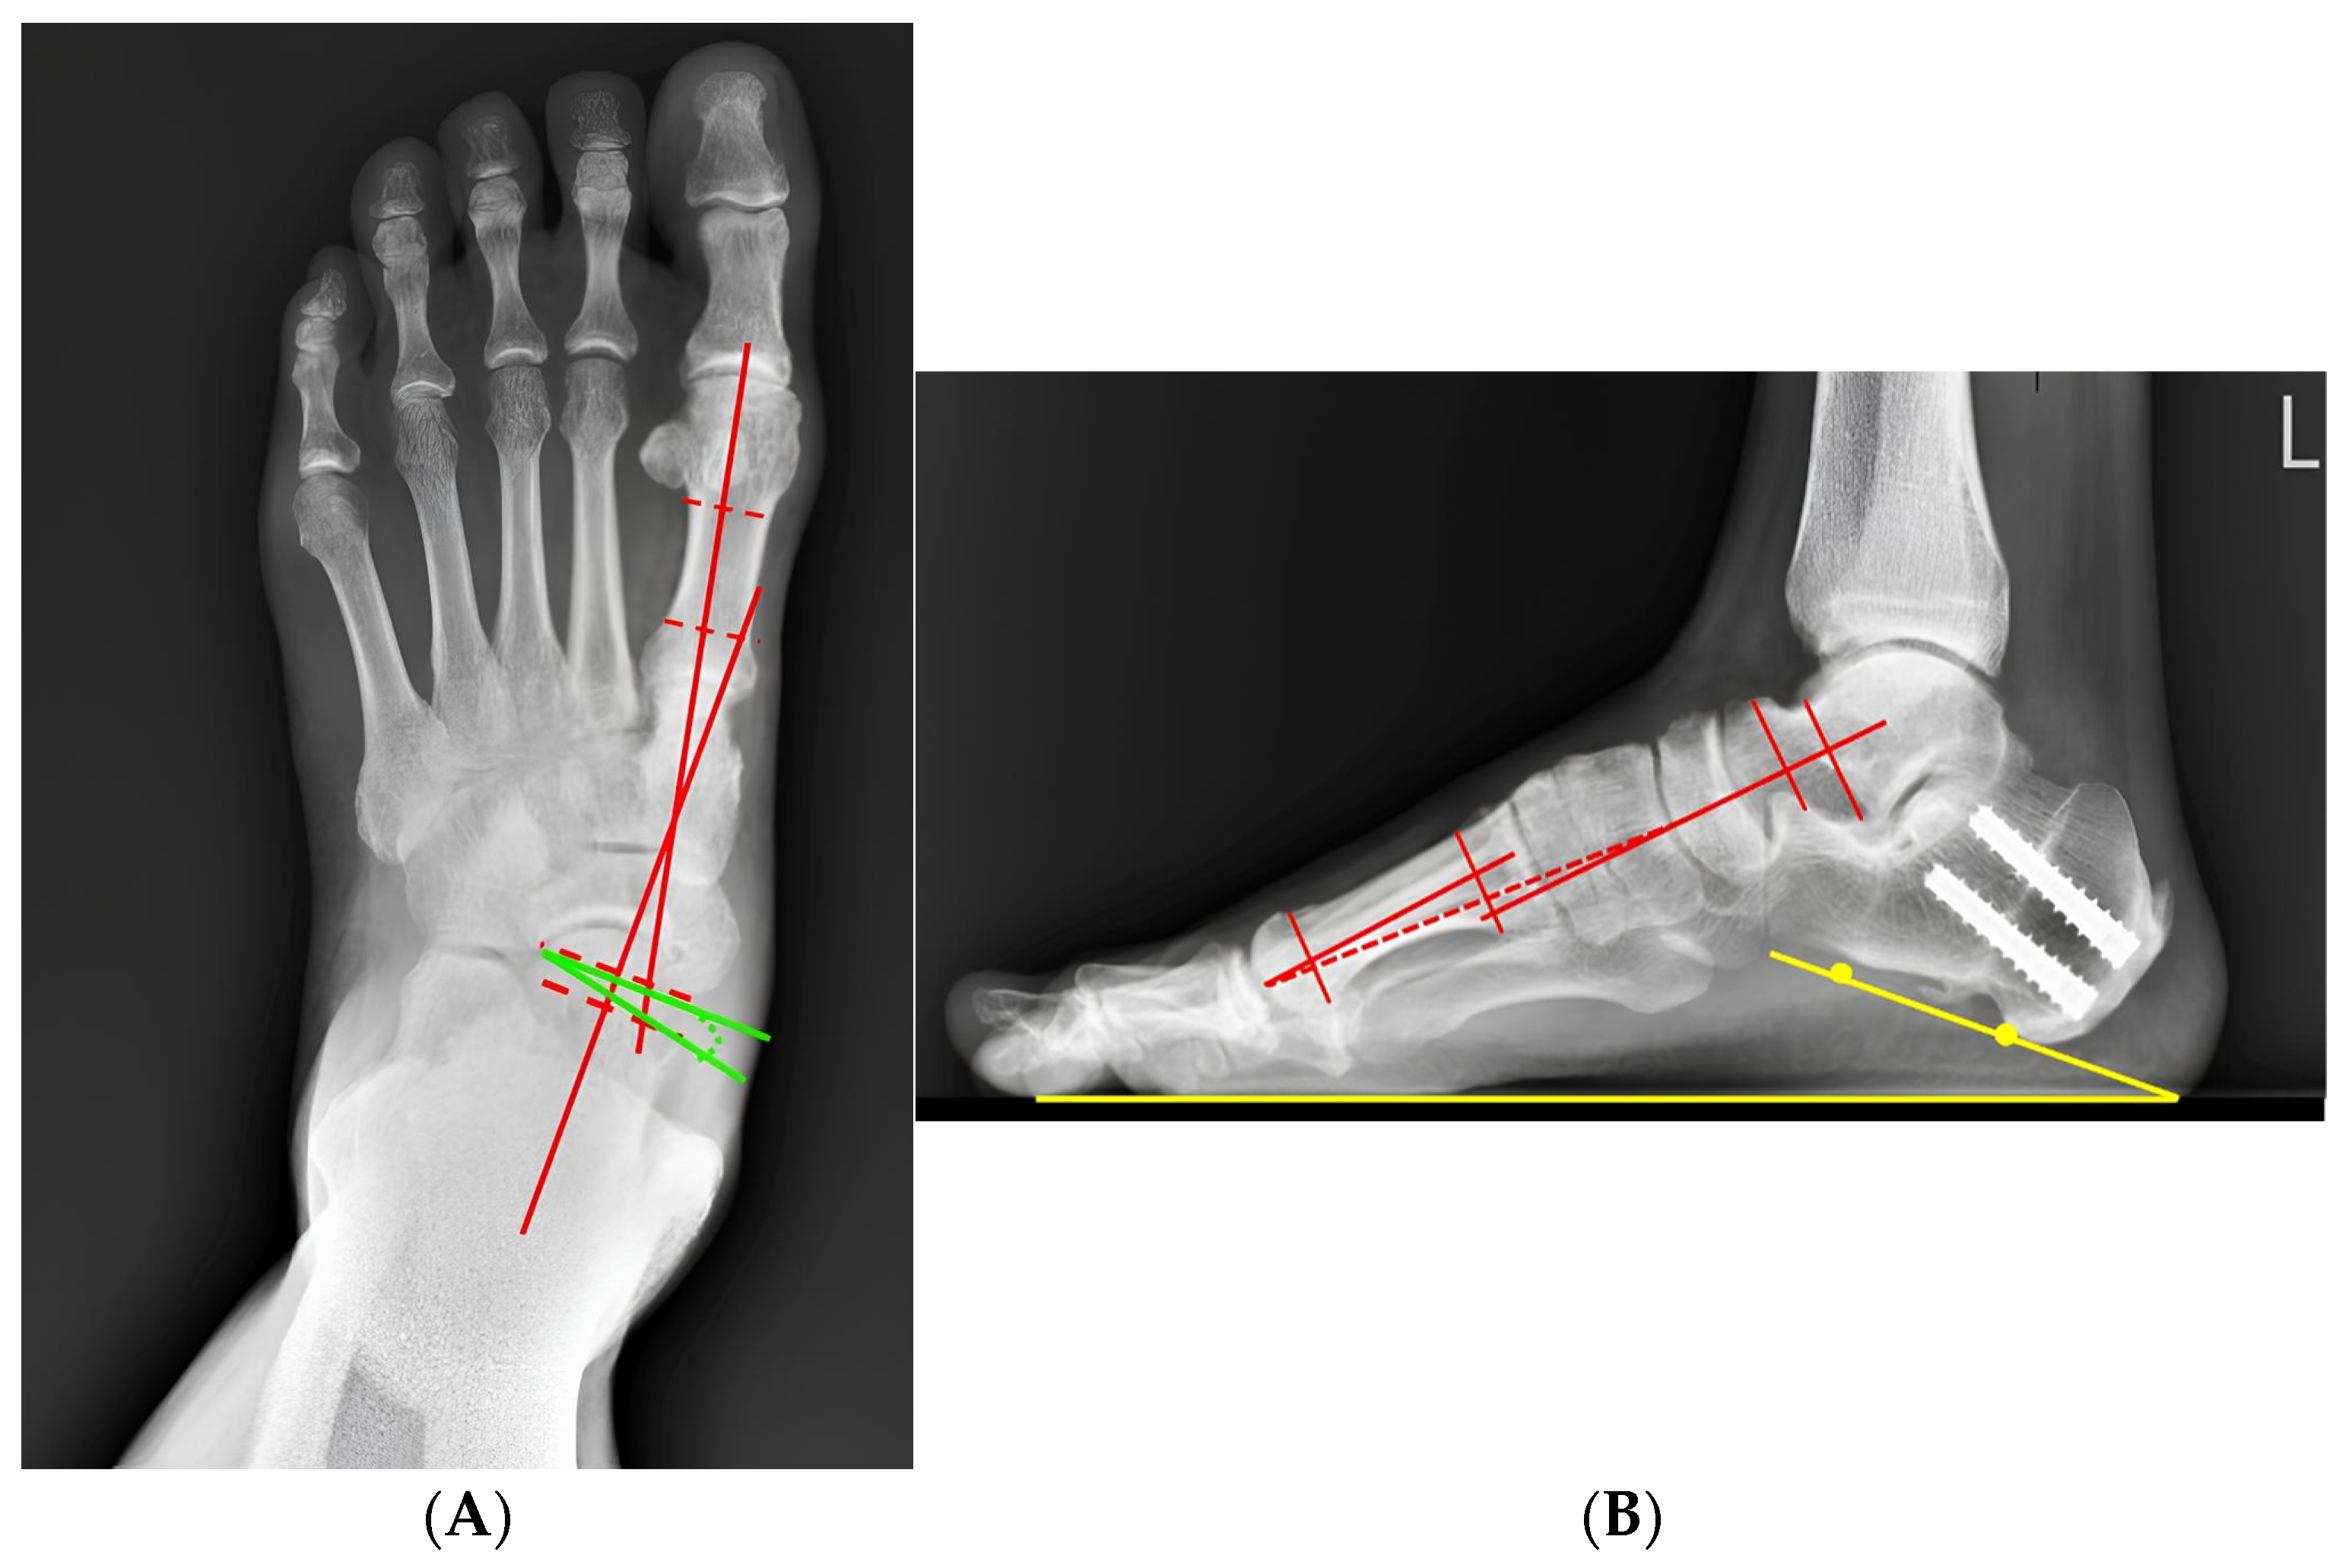

3.6. Representative Case

| Parameter | Preoperative | Postoperative | 24 Months of Follow-Up | p-Value |

|---|---|---|---|---|

| Meary angle (AP, °) | 24.2 ± 7.4 | 9.2 ± 4.1 | 8.6 ± 4.1 | <0.001 |

| Meary angle (Lateral, °) | 9.96 ± 2.3 | 1.92 ± 1.4 | 2.05 ± 1.6 | <0.012 |

| Calcaneal pitch (°) | 10.64 ± 4.87 | 15.78 ± 3.33 | 15.55 ± 4.25 | <0.01 |

| Talonavicular coverage angle (°) | 14.53 ± 6.67 | 3.46 ± 1.56 | 3.58 ± 0.78 | <0.024 |